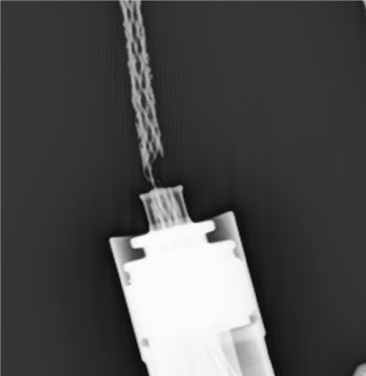

Figure 2. X-ray image of LVAD driveline revealing significant damage with only 1 of 6 wires intact

A 26-year-old female with dilated cardiomyopathy underwent HeartMate II LVAD implantation as destination therapy, eventually required device exchange on November 29, 2012 due to infection, and was supported with an EPC controller. Patient contacted the implanting centre reporting red heart alarms with associated chest pain and unusual LVAD sensations. After air transportation to the implanting centre and connection to the display monitor, speed drops from 9400 RPM to 0 RPM were noted with associated red heart alarms, chest pain, and hemodynamic decompensation. LVAD driveline was completely exposed, silicon connection was compromised, and plastic wire covering was blackened from wear and exposure over weeks (Figure 1). A controller exchange to a new pocket controller did not bring resolution to these events. The driveline was manipulated, pinched together, and pressed against the insertion section at the controller to minimize the frequency of pump stopping. Central access was established should inotrope support be required, imaging studies were obtained, and communication with Abbott was undertaken regarding potential external driveline repair. X-ray of the driveline revealed significant damage with only 1 of 6 wires intact (Figure 2). The patient proceeded with emergent surgical exchange to replace the damaged driveline which was uneventful and was extubated the same day. The patient continued to require manual stabilization of the driveline to maintain electrical contact and prevent pump stoppage during OR preparation and surgical dissection prior to device exchange.

Driveline damage can occur with repeated wear over time. Driveline compromise prompts specific alarms with newer HeartMate pocket controllers. This patient was supported with the older EPC controller and did not have access to a display module or backup controller at the time of the events described; thus, red heart alarms that transpired left a broader differential of potential causes. Patients supported with EPC controllers with suspected driveline fracture should be maintained on battery support as outlet power can prompt a short to ground and pump stoppage. This patient’s driveline had silicone damage and discontinuity for some time as the clear covering around the driveline wires had become dark brown with environmental exposure (Figure 1). Extent and location of driveline compromise can be difficult to evaluate with x-ray images; however, this patient’s images were unique in the clear demonstration of fractures. Generally, external splicing repair of the driveline is attempted before surgical repair if only one of the two paired wires in a driveline is suspected to be damaged. If driveline damage is extensive, thought to be internal, or if hemodynamic compromise is associated, more urgent operative intervention for exchange of the LVAD to replace the driveline needs to be considered. For this patient, manipulation of the driveline even a few millimetres resulted in pump stoppage and hemodynamic collapse; the extent of presentation in this case was dramatic and required constant human stabilization during all the time preceding definitive exchange. In some situations where patients are deemed non-operative, an ungrounded cable may be provided. Early identification of suspected LVAD driveline fracture is necessary to allow for patient stabilization, verification and ascertaining extent of compromise and evaluation of appropriate interventions to sustain ongoing LVAD support.